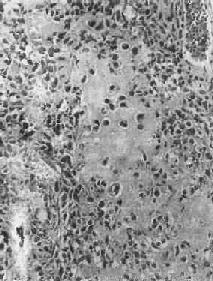

镜下,肿主要由单核基质细胞及多核巨细胞等两种细胞组成(图17-6),间质血管丰富。基质细胞为梭形、卵圆形或圆形,细胞境界不清楚,常见胞浆突起。细胞核较大,染色质量中等,可具有一个核仁。多核巨细胞常较均匀地散布在基质细胞之间,是为本的特点。多核巨细胞的直径常为30~60μm,核数一般为15~20个,最多可达100个以上,常聚集在细胞的中央。核的形态与单核基质细胞相似。细胞边界不规则,但分界较清楚,胞浆丰富,略呈嗜碱性,有时还可见含大量脂类的泡沫细胞。本间质血管丰富,有多少不等的胶原纤维。肿本身无成骨现象,但有时见有类骨组织及新生骨小梁,常见于纤维组织的周围,可能是一种反应性新骨形成或病理性骨折后形成的骨痂。

骨巨细胞<a href=瘤(Ⅰ级)"/>

图17-6 骨巨细胞(Ⅰ级)

由大量基质细胞和多核巨细胞两种细胞组成